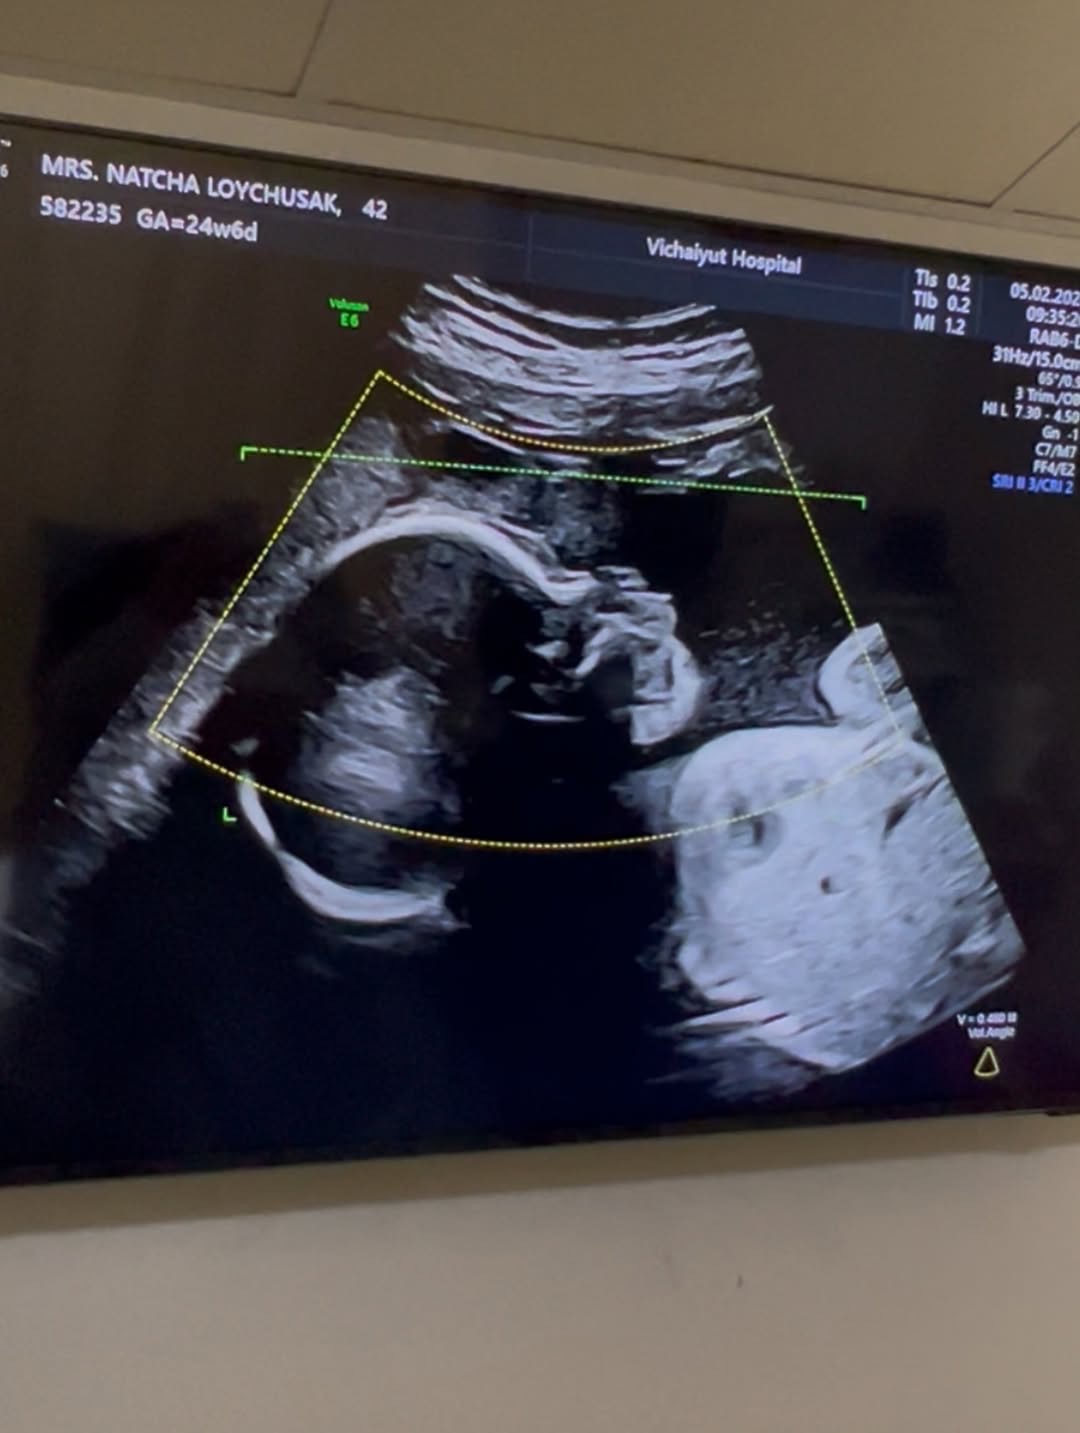

ทำเอาแฟน ๆ เตรียมสมัครเป็นพี่เลี้ยงออนไลน์กันล่วงหน้า เมื่อ เจมส์ เรืองศักดิ์ ลอยชูศักดิ์ ออกมาแชร์โมเมนต์อบอุ่น อัปเดตการตั้งครรภ์ของภรรยาคนสวย ครูก้อย นัชชา ลอยชูศักดิ์ พร้อมเผยภาพอัลตราซาวด์ของลูกสาวคนที่ 2 “น้องมีเมตตา” ที่ตอนนี้อายุครรภ์ครบ 6 เดือนแล้ว

จากภาพอัลตราซาวด์เผยให้เห็นเค้าโครงใบหน้าของน้องมีเมตตาอย่างชัดเจน นอนยิ้มหวานละมุน แถมจมูกโด่งสะดุดตา เรียกได้ว่าน่ารักน่าชังตั้งแต่อยู่ในท้อง โดยพ่อเจมส์เขียนแคปชันด้วยความเอ็นดูว่า “แม่หนูมีเมตตาของฉัน จมูกโด่ง ยิ้มหวาน” พร้อมอัปเดตว่า คุณหมอกล้วย แพทย์ผู้ดูแลครรภ์ครูก้อย ยืนยันว่าลูกน้อยแข็งแรงสมบูรณ์ พัฒนาการเป็นไปตามเกณฑ์ทุกด้าน ก่อนจะปิดท้ายด้วยมุกขำ ๆ สไตล์คุณพ่อว่า “สินค้าเด็กเข้าได้เลยครับ ( ฮาาา…. )” ทำเอาแฟน ๆ เข้ามากดไลก์และคอมเมนต์ชื่นชมความน่ารักของน้องมีเมตตาอย่างล้นหลาม